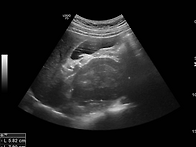

hcc ? - > hemangio..

하늘호수 26.05.09* HBV carrier1. 간실질정상( ), 지방간( O ), 거친에코( ..